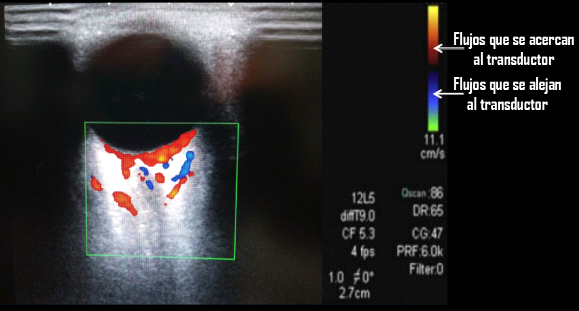

Conventionally, those flows that approach the transducer (in the cerebro-ocular direction) are represented in red, and inversely, those flows that move away from the transducer (in the oculocerebral direction) are represented in blue (Figure 1).

Figure 1 Direction of flow according to the color map.

Depending on the color map (Figure 1) any vascular structure approaching the transducer is impregnated with a positive value or red color and conversely those moving away, negative or blue color, so the arteries examined in our study were visualized in red color. In this way, we proceed to recognize the presentation of the ophthalmic artery in its medial (nasal) path with respect to the path of the optic nerve; the central retinal artery, contained as well as its accompanying vein, the central retinal vein, in the adventitial sheath of the optic nerve; and the short posterior ciliary arteries a few millimeters from the area of recognition of the central vessels.